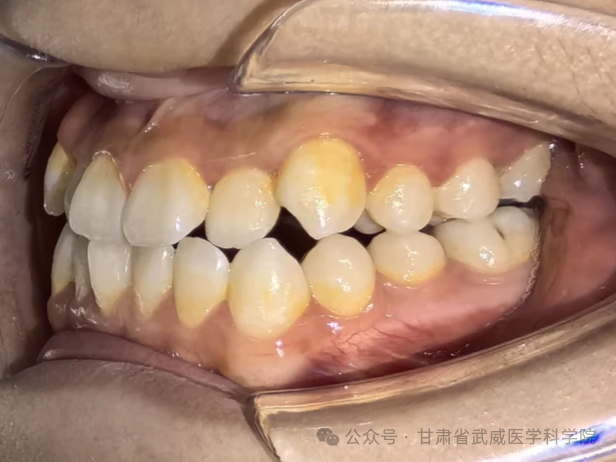

牙列不齐,医学上称为“错颌畸形”,是指儿童在生长发育过程中,由先天的遗传因素或后天的环境因素(如疾病、口腔不良习惯、替牙异常等)导致的牙齿、颌骨、颅面的畸形。

·异常磨损: 牙齿排列不齐会导致咬合力量分布不均,个别牙齿过度磨损,出现酸痛、敏感甚至断裂。

·“地包天”: 下牙包住上牙,会导致面中部凹陷,形成“月牙脸”。

·龅牙/小下巴: 上颌前突或下颌后缩,导致开唇露齿,嘴唇无法自然闭合。

·偏颌: 长期单侧咀嚼导致脸型不对称,变成“大小脸”。